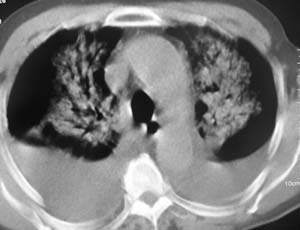

以下是引用zyx168在2007-1-21 17:08:00的发言:[br]男,71岁,咳嗽、胸闷10天余,咯血1天。[br]两肺大片状密度均匀影,充气支气管征象明显,左房增大,双侧胸腔内新月形液性密度影。[br]考虑:1,心源性肺水肿伴双侧胸腔中等量积液;[br] 2,两肺肺炎?